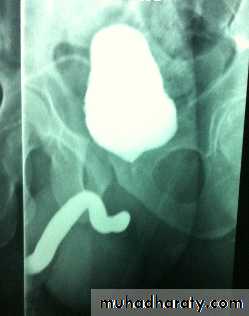

What's This Study & Abnormal Finding

Retrograde urethrography showing stricture of the bulbar part of urethra.